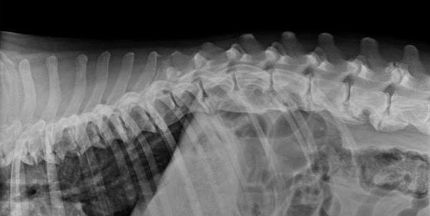

We work in cooperation with your veterinary!

Ideally you are coming after consulting your vet. With a reliable diagnosis we can work out an individual therapy plan for your horse or dog.

About Physiotherapie

Physiotherapy and massage belong to the oldest remedial methods of the humanity, recordings were already found 2000 years ago. It is the human hand, the tactile, sensomotoric and sensitive charms straight on the body of the patient transfers around the healing process to stimulate.

Operational areas of the physiotherapy

– Therapeutic care after injuries, accidents and degenerative problems